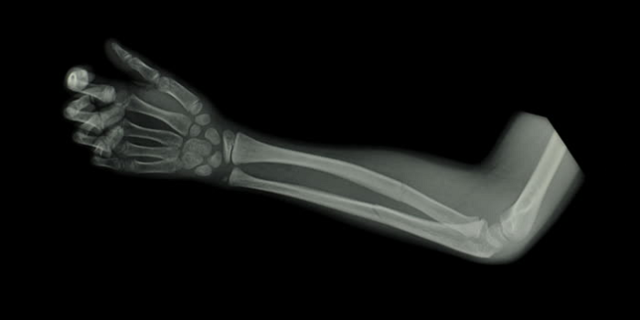

Семилетняя второклассница при прыжке упала. Как результат, открытый перелом со смещением обеих костей правого предплечья. По словам учителя физкультуры Юрия Ковальчука, он действовал согласно инструкции, увидев, что ученица сломала руку, он забрал ее с места, где произошла травма.